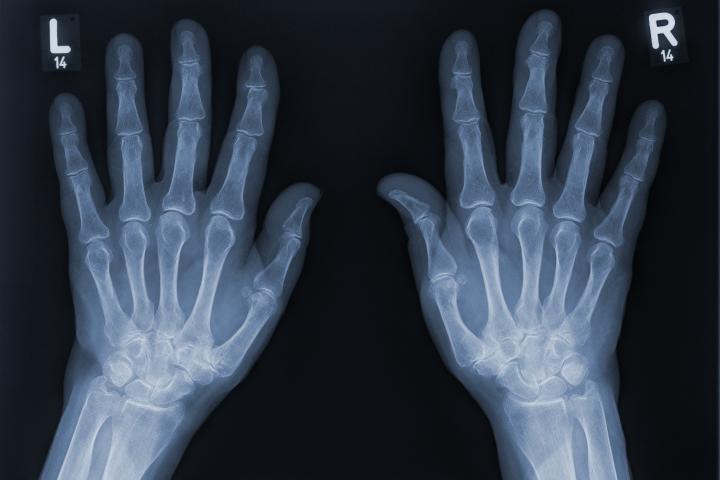

Pero, ¿alguna vez te has preguntado por qué este dedo es tan diferente al resto? Mientras los demás tienen tres huesos o falanges, el pulgar solo tiene dos. Y esta diferencia no es casualidad, sino el resultado de un largo proceso evolutivo que cambió para siempre la forma en que los humanos interactúan con el mundo.

A simple vista, podría parecer que tener menos articulaciones limitaría el movimiento del pulgar, pero en realidad sucede todo lo contrario. Si el pulgar tuviera solo una, sería rígido y poco funcional; y si tuviera tres, como el resto de los dedos, sería demasiado largo, débil y difícil de controlar.

Con dos huesos, en cambio, logra un equilibrio perfecto entre estabilidad, movilidad y fuerza. Gracias a esta estructura, el pulgar puede oponerse a los otros dedos, permitiendo una amplia variedad de movimientos que van desde sostener un lápiz o un teléfono móvil hasta abrochar un botón o abrir una botella.

Cada dedo tiene tres falanges (distal, media y proximal), excepto el pulgar, que solo cuenta con la proximal y la distal. Esta diferencia, junto con los músculos, tendones y ligamentos que lo acompañan, permite una destreza única que ninguna otra especie posee.